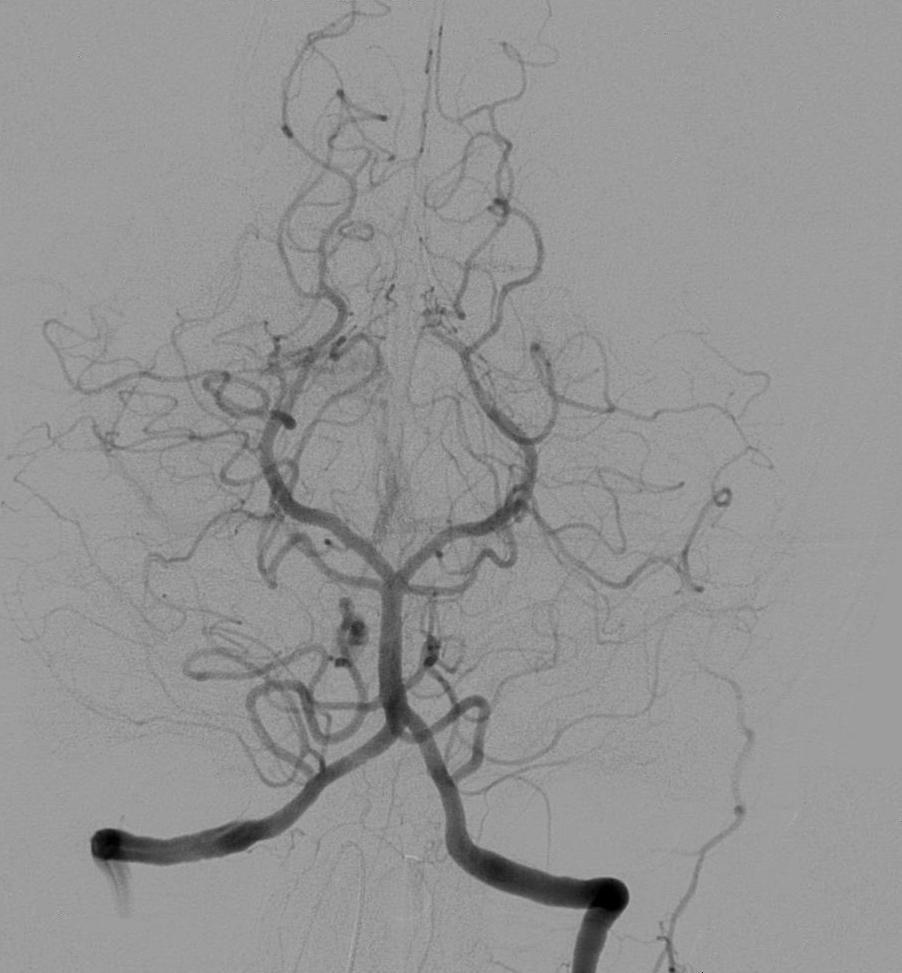

Angiography¶

Angiography is a medical imaging techniques used to visualize the inside of blood vessels and organs of the body, performed by injecting a radio-opaque contrast agent into the blood vessels and imaging using X-ray based techniques such as fluoroscopy.

Figure 11:Cerebral angiography, injection in the left vertebral artery, with retrograde flow in the contralateral vertebral artery, the basilar artery and the posterior communicating artery. The posterior cerebral circulation can be seen, including the posterior part of the Circle of Willis. Image courtesy of Lipothymia, Public domain, via Wikimedia Commons, accessed here on 2026-02-04.